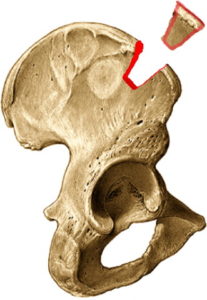

Het voorste botuitsteeksel van het schouderblad (processus coracoïdeus) wordt losgemaakt en samen met de pezen erop getransplanteerd naar de voorzijde van de kom van de schouder (glenoid). Dit stukje bot wordt vastgezet met 2 schroeven. Het stukje bot zorgt voor een groter oppervlak van de kom, de pezen die erop vastzitten zorgen voor een bijkomende stevigheid zodat de schouder niet meer uit de kom kan.

Een stukje bot van 3x2cm wordt weggenomen ter hoogte van de bekkenkam en nadien vast geschroefd ter hoogte van het letsel van de kom. Op die manier wordt het oppervlak van de kom groter gemaakt.